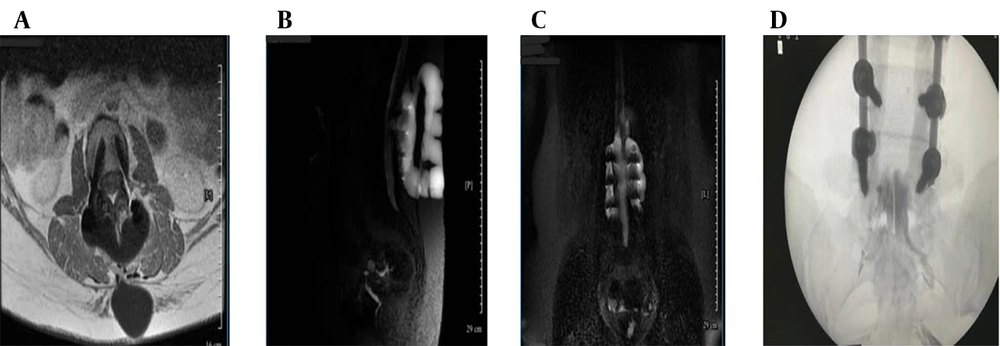

Ongoing symptoms prompted further evaluation. The CT myelography was unavailable, so magnetic resonance (MR) myelography was used instead, revealing an active CSF leak at L4-L5 (Figure 1B - D and 2A), confirmed by contrast extravasation (Figure 2B and C). Given the failure of surgery and conservative therapy, an EBP was indicated. Direct lumbar access was avoided for three main reasons: (1) Postoperative fibrosis and adhesions at L4-L5, (2) risk of cephalad migration reducing efficacy, and (3) procedural difficulty associated with reoperated anatomy. A caudal approach was chosen for broader epidural spread, avoidance of manipulation of the surgical site, and minimizing procedural risks. Informed written consent was obtained from the patient for both the medical procedure and publication of this case report, in accordance with the Declaration of Helsinki. Ethical approval for this work was granted by the Research Ethics Committee of Tehran University of Medical Sciences (IR.TUMS.IKHC.REC.1404.152).

Magnetic resonance (MR) myelography and intervention (A - D): A, axial T1-weighted post-contrast magnetic resonance imaging (MRI) confirming enhancing epidural fluid; B, sagittal MR myelography showing contrast extravasation at L4-L5; C, coronal MR myelography confirming cerebrospinal fluid (CSF) tracking to sacral levels; D, fluoroscopic image showing catheter placement and cranial contrast spread.

The patient was transferred to the operating suite for a catheter-guided CEBP under fluoroscopic guidance in sterile conditions and monitored anesthesia care. After standard positioning in the prone posture, with a pillow under the abdomen to optimize sacral access, the sacral hiatus was palpated and confirmed fluoroscopically. An 18-gauge Tuohy needle was introduced through the sacrococcygeal ligament and advanced under real-time fluoroscopic guidance into the caudal epidural space (Figure 2D). Following successful needle placement, a flexible epidural catheter was inserted through the Tuohy needle and advanced cranially within the posterior epidural space. Catheter navigation was performed under intermittent fluoroscopy with contrast injection to assess cranial spread and ensure accurate positioning. The catheter tip was advanced approximately 26 cm cranially from the sacral hiatus to reach the L4-L5 level, precisely corresponding to the dural defect identified on pre-procedural MR myelography. To facilitate controlled injection dynamics and improve maneuverability within the epidural space, approximately 20 cm of the catheter was trimmed prior to reinsertion. Epidurography confirmed accurate epidural positioning, demonstrating symmetric and progressive cranial dispersion of contrast without vascular opacification or inadvertent subarachnoid entry. Real-time anteroposterior–lateral fluoroscopic monitoring guided catheter navigation and ensured optimal placement despite postoperative anatomical distortion.